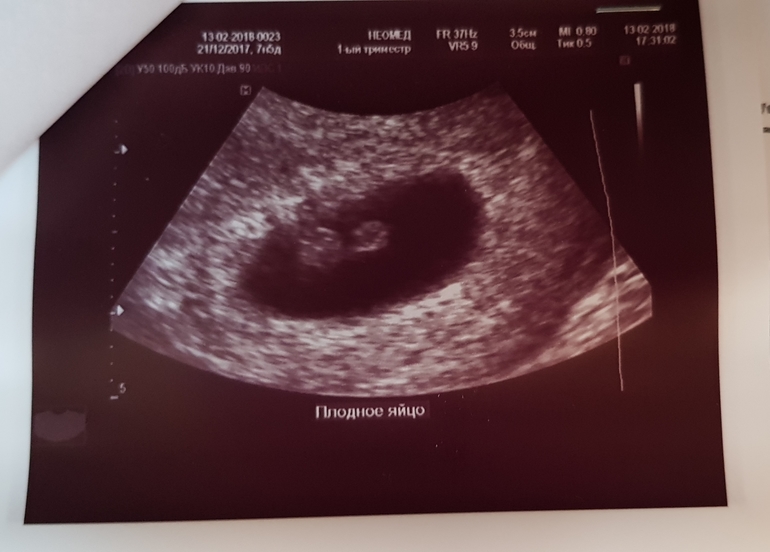

Повторное узи в 7 недель

А вчера нашли мою бусинку, ктр 8мм, что соответствует 7 неделям,сердечко бьется 133 уд/мин , дали послушать. Беременность развивается хорошо. Но у меня гипертонус передней стенки, из за этого матка неправильной формы, не круглая, а овальная,поставили угрозу прерывания беременности. Сегодня сходила к своей Г. Она сразу же выписала направление на стационар, хотя читаю что у многих девочек такое было, лечились дома. Я так не хочу лежать в больнице, у меня там депрессивное состоянии начинается. Дома спокойнее ведь, муж рядом и доченька. Не по наслышке знаю про наше гинекологическое отделение, и отношение врачей. Не знаю как быть, понимаю что нужно лечь сохранять крошку. Или можно как договориться с врачом и приходить например на процедуры? У кого была такая ситуация, поделитесь пожалуйста.